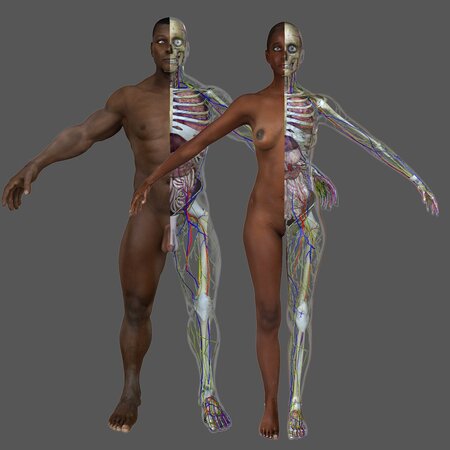

It contains:

Respiratory system | Heart | Diaphragm | Digestive system | Kidneys with bladder | Liver | Stomach